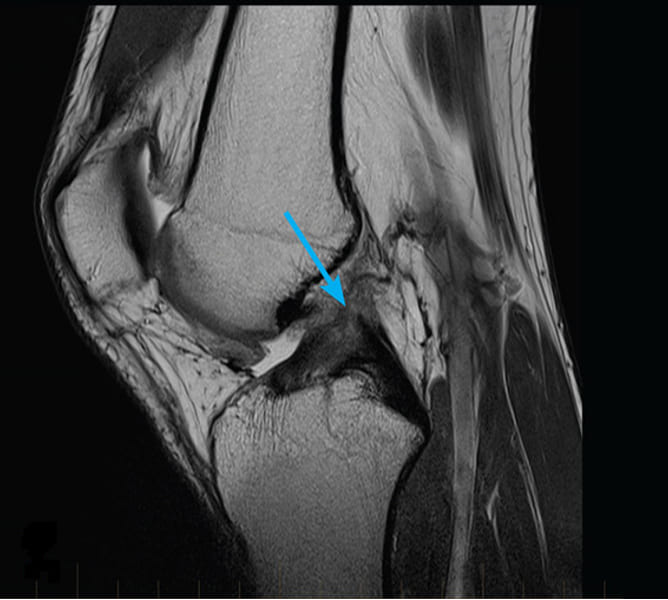

Podívejte se na tyto obrázky, můžete vidět, že na obrázku vpravo není žádný kloubní prostor, kosti se o sebe třou a způsobují silnou bolest. A tento proces je velmi těžké zastavit! Za pár let se ten člověk stane invalidním a už se nebude schopen sám živit.

Markéta Svobodová: Především jsou to vážná zranění a napětí. Nadváha také hodně zatěžuje vaše klouby. Sedavý způsob života, stres, nadbytek soli a cukru ve stravě, to vše změkčuje chrupavčitou tkáň, opotřebovává ji a ředí. Při každém novém pohybu se chrupavka ničí a deformuje a kosti se o sebe začnou třít, což způsobuje nesnesitelnou bolest.

Nežertujte s artrózou a artritidou! Onemocnění kloubů vás posadí na invalidní vozík za necelé 3 roky!

Novinář: Kdy má zazvonit budík? Jaké příznaky by vás měly varovat?

Markéta Svobodová: Příznaky jako:

- Bolest při ohýbání kloubů.

- Necitlivost v prstech rukou a nohou.

- Křupavé při popíjení.

- Otok a zarudnutí kloubu.

- Pocit písku v kloubech.

- Neodůvodněné zvýšení teploty.